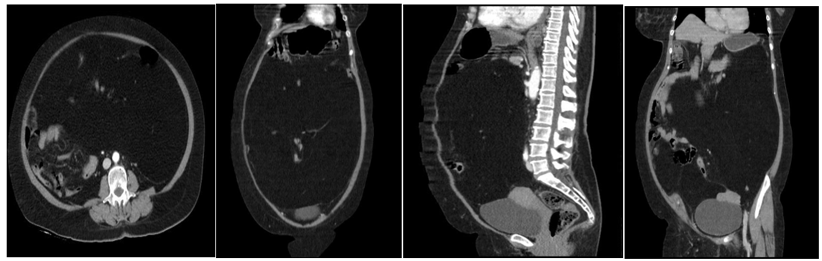

Figura 2. Tomografía computarizada abdomino-pélvica

La tomografía computarizada abdomino-pélvica realizada el 14/12/2023, reportó lesión homogénea hipodensa, de predominio graso (-127 UH), con focos isodensos periféricos, no realzan al medio de contraste, desplazan asas intestinales lateralmente hacia la derecha. No se observan adenopatías, no liquido libre en cavidad, reportando un diagnóstico por imagen de lesión ocupativa intraabdominal sugestiva de lipoma mesentérico (figura 2).

El lipoma mesentérico de nuestra paciente se manifestó por dolor abdominal sin signos de obstrucción intestinal, pero si un aumento progresivo de la circunferencia abdominal, siendo en nuestro caso la tomografía la que mostró una lesión mesentérica típica con gran hipodensidad que abarcaba prácticamente la totalidad de la cavidad abdominal, lo que nos orientó al diagnóstico y poder decidir la conducta terapéutica apropiada.